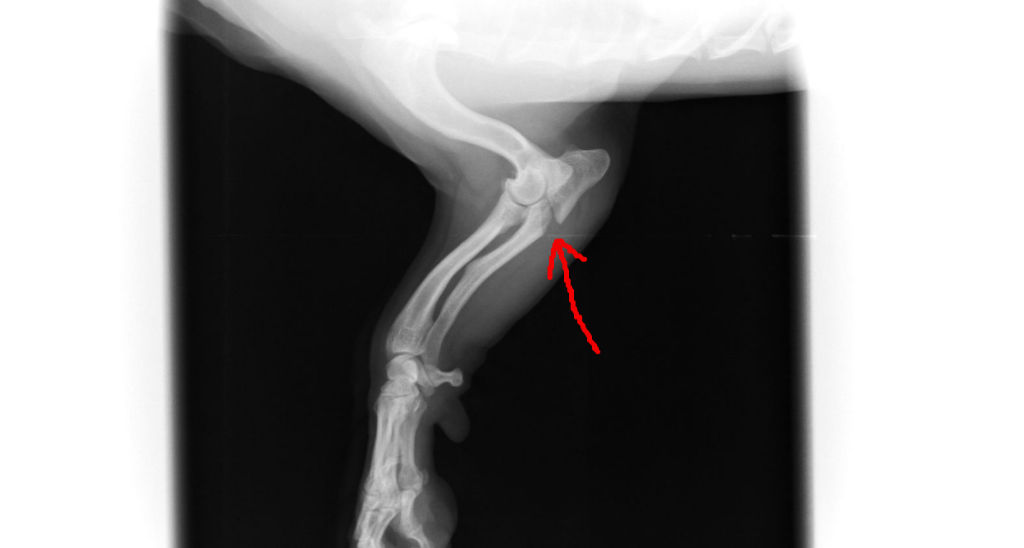

Jun 09, 17 · そして、右レントゲン検査所見のほか、前記五において認定したような肺挫傷による症状ないし所見が二〇日午後二時の時点において出現していたことを認めるに足りる証拠はないから、仮に被告が肺部の観察を目的とした条件の良いレントゲン写真を撮影Jul 03, 19 · 犬の肺挫傷って治るのでしょうか。愛犬が肺挫傷になって入院しました。私は仕事中でどうしても抜けれなかった為義理祖母が病院へ連れてってくれました。肺挫傷で現在入院中で病院側 は様子を見るそうです。犬種は甲斐犬で老犬Mar 30, 17 · 肺挫傷の診断には画像診断(胸部レントゲン検査及び胸部ct検査)が有効です。 特に 胸部CT はレントゲンと比較して、肺挫傷の検出率は高いと報告されています (Radiology 19;) 。

こんな病気を治療しています 葉山どうぶつ病院

Vmnセミナー情報 Veterinary Medical Network